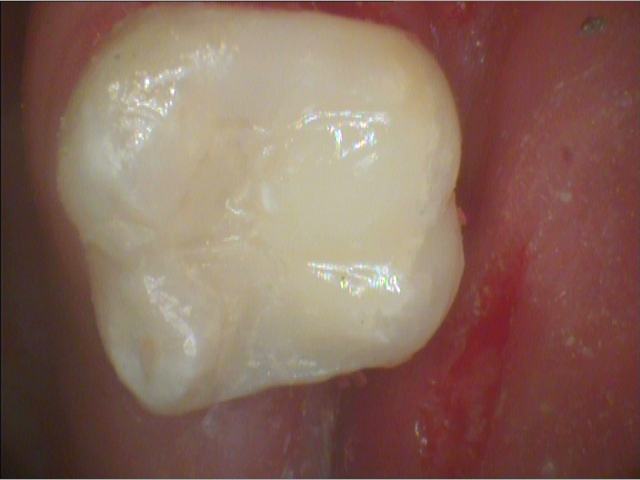

Fig. 3 Fig. 4

Next, 37% phosphoric acid was applied for 15 seconds as a total etch on the enamel, dentin and Biodentine. The etchant was then rinsed off. Adhesive was applied, air thinned and cured. A low stress bulk fill flowable was placed and topped with a universal composite resin then finished and polished (Fig. 4). Thus, this tooth has been restored and the pulp has been left intact and vital. The Biodentine layer, acting as a indirect pulp cap and dentin replacement, will presumably stimulate tertiary dentin formation and keep this pulp healthy. Considerable tooth structure has been saved and the long-term prognosis much improved. This makes me feel like a dental hero, saving this young patient’s tooth from endodontic and crown treatment.